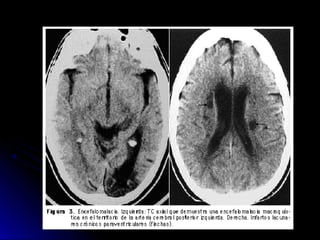

• 34.

Ubicación de laslesiones en TAC-RNM